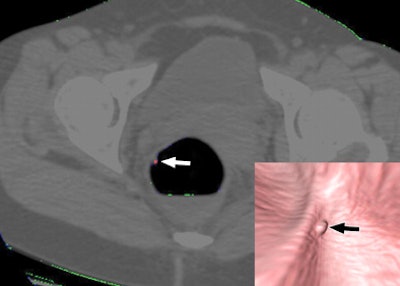

| Above, a 45-year-old woman with 6-mm hyperplastic polyp in the rectum. On CT colonographic images in supine view, part of polyp (arrow) is colored red and detected with computer-aided detection scheme on both supine and prone datasets. Note endoluminal appearance of polyp on each dataset (right lower corner). Republished with permission of the © American Roentgen Ray Society, by Se Hyung Kim, Jeong Min Lee, Joon-Goo Lee, Jong Hyo Kim, Philippe A. Lefere, Joon Koo Han, and Byung Ihn Choi, from AJR 2007; 189:41-51). |